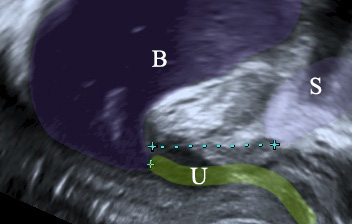

Η ουροδόχος κύστη εκκενώνεται μέσω της ουρήθρας. Πρόκειται για μια σωληνοειδή κατασκευή με μήκος περίπου 2.5-4 εκατοστών, η οποία χρησιμεύει στην αποβολή των ούρων. Πέραν όμως αυτής της της ιδιότητας, έχει γύρω της ένα σύμπλεγμα 3 διαφορετικών μυών, γνωστό και ως σφιγκτηριακό σύμπλεγμα της ουρήθρας, το οποίο είναι κυρίως υπεύθυνο για την αύξηση της πίεσης εντός της αυτής.

Η άνοδος της πίεσης στην κύστη κατά τον βήχα στις υγιείς γυναίκες οδηγεί σε ταυτόχρονη, παρόμοια αύξηση της πίεσης εντός της ουρήθρας, καθώς και τα δύο όργανα συμπιέζονται κόντρα στο υπόστρωμά τους, γνωστό και ως ηβοτραχηλική περιτονία. Έτσι η πίεση στην ουρήθρα παραμένει υψηλότερη εκείνης στην κύστη και η γυναίκα δεν χάνει ούρα. Αυτό το φαινόμενο λέγεται επαγωγή.

Αν όμως ο υποκείμενος ιστός της ουρήθρας έχει χαλαρώσει (ηβοτραχηλική περιτονία), τότε η ουρήθρα γίνεται υπερκινητική. Κάθε φορά που η ασθενής βήχει, η ουρήθρα “ξαπλώνει” και η πίεση εντός αυτής δεν μπορεί να αυξηθεί – έτσι η λεγόμενη επαγωγή της πίεσης αποτυχαίνει. Η πίεση εντός της κύστης αυξάνεται ραγδαία, εκείνη εντός της ουρήθρας όχι, έτσι η πρώτη υπερνικά τη δεύτερη και έχουμε τη δυσάρεστη απώλεια ούρων.